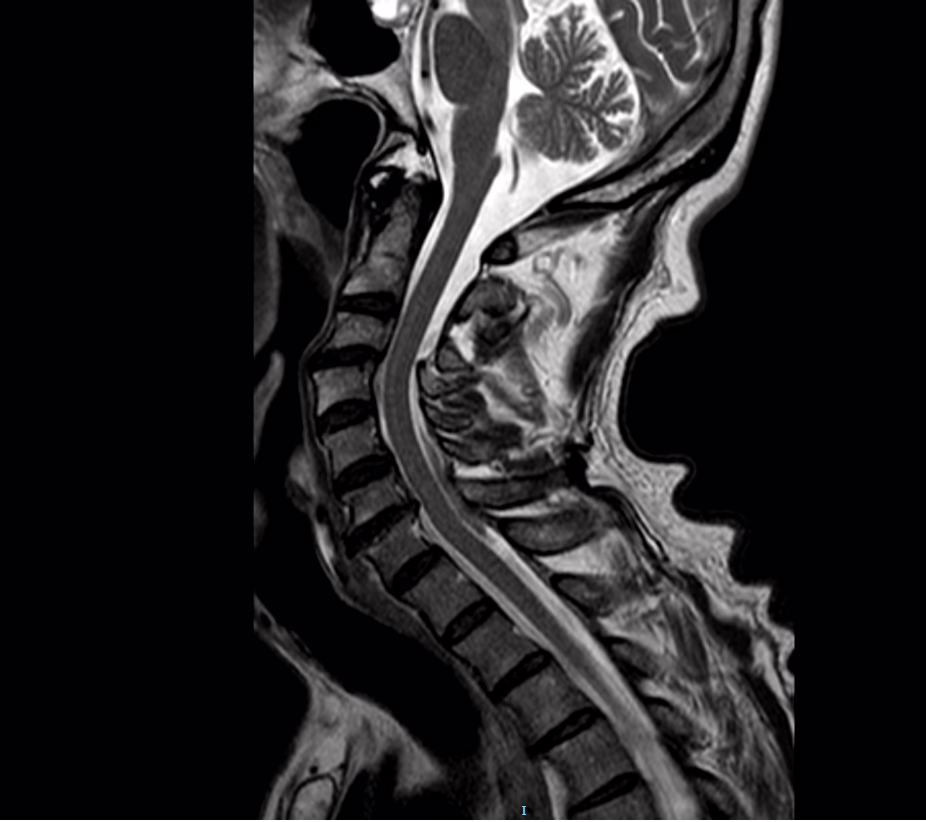

Los cuerpos vertebrales visibles son de morfología e intensidad de señal normal en las distintas secuencias, sin lesiones destructivas o infiltrativas con formacion de osteofitos en bordes anteriores de los cuerpos vertebrales . Los componentes de arcos posteriores sin anormalidades detectables mediante este método de imagen. Unión cráneo-cervical sin alteraciones.

El cuerpo vertebtal de C3 con discreta retrolistesis

Los discos intervertebrales se tiene con intensidad de señal disminuida en secuencias T2 mostrando a disminución del espacio C6-C7

Se tiene aumento en la lordosis cervical

Se tiene cambios degenerativos de las plataformas a nivel de C6-C7

En conducto raquídeo la médula es de calibre normal, sin lesiones expansivas, sin zonas de adelgazamiento focal sugestivas de atrofia. No compresiones extrínsecas sobre la misma. Su intensidad de señal es normal tanto en T1 como en T2. Unión bulbo-medular conservada.

A nivel de espacio C6-C7 se tiene complejo disco-oseofitario con obliteracion del espacio subaracnoideo anterior

Complejo disco-osteofitario C6-C7

Discreta retrolitesis de C3

Cambios de deshidratación del núcleo pulposo de los discos

Cambios degenerativos de las plataformas a nivel e C6-C7

Cambios de espondiloartropatia degenerativa